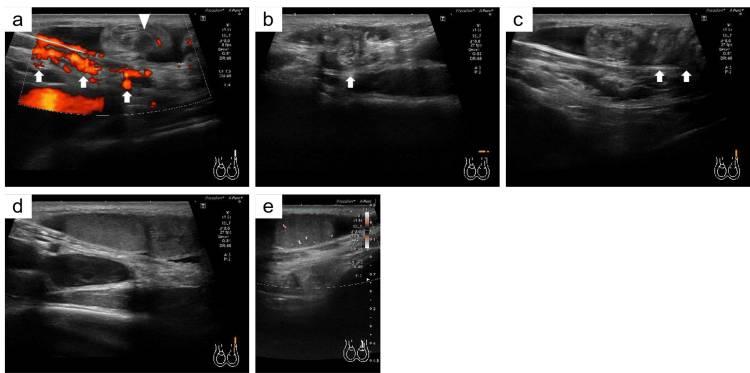

经检查,左腹股沟区域出现肿胀(2×2 cm)并伴有轻度压痛。阴囊的左半部分为空,右侧睾丸大小、位置正常。超声检查显示,左精索位于腹股沟管内螺旋扭转(图1a-1c)。左侧睾丸位于腹股沟管上方,回声正常,但小于右侧正常睾丸(右侧睾丸,41×28×16 mm;左侧睾丸,18×18×8 mm;图1d)。多普勒超声显示睾丸内血流正常(图1e)。

图1 a) 箭头显示腹股沟管内的精索。三角形显示腹股沟管上方的精索。b) 精索指向体表(箭头)。c) 箭头显示精索有多处扭曲。d) 左睾丸回声正常。e) 能量多普勒超声显示左睾丸血流保持